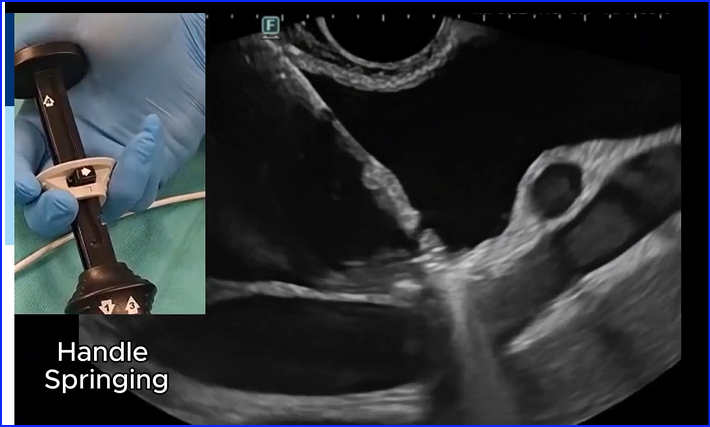

Failure of release of the Hot AXIOS distal flange: "handle springing" as a rescue technique thieme-connect.de/products/ejour… #GItwitter #Metwitter #EUS #AXIOS